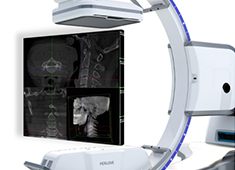

國(guó)產(chǎn)骨科手術(shù)機(jī)器人助推手術(shù)智能化的實(shí)現(xiàn)

一批高科技醫(yī)療技術(shù)企業(yè)涌入手術(shù)機(jī)器人設(shè)備研發(fā)領(lǐng)域,還有一些國(guó)內(nèi)的影像設(shè)備廠商也紛紛在這個(gè)賽道發(fā)力。擁有二十年醫(yī)學(xué)影像經(jīng)驗(yàn)的普愛醫(yī)療,在推出“平板三維C形臂+骨科手術(shù)機(jī)器人”的全流程解決方案,便吸引了市場(chǎng)的廣泛關(guān)注。...